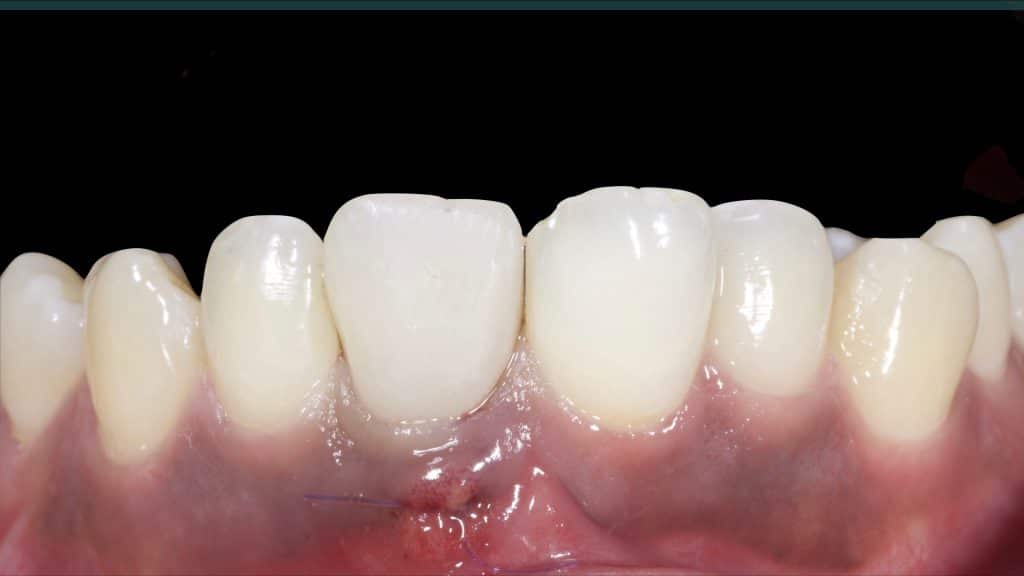

Immediate post-op